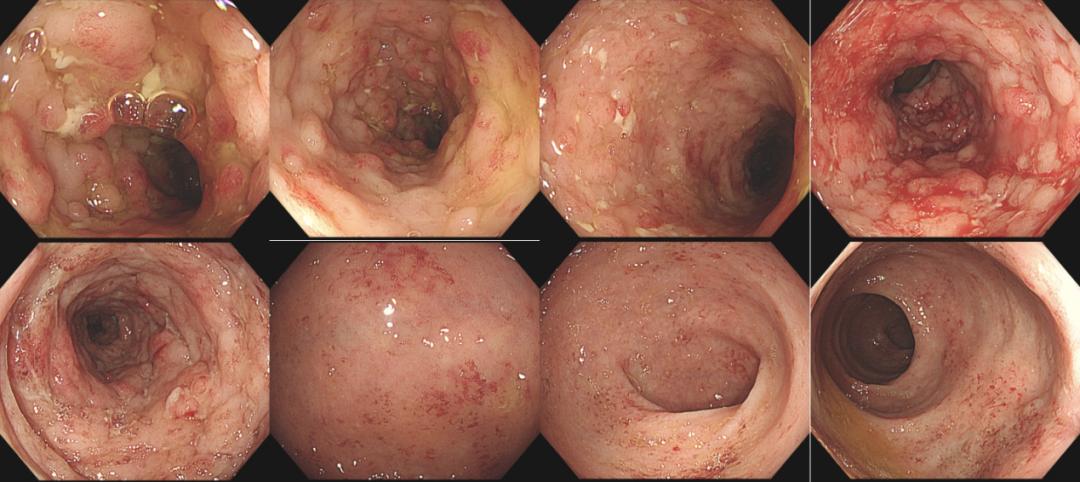

20220110肠镜检查:插镜至回末,距肛缘28~10cm可见四壁黏膜鹅卵石样表现、散在溃疡、小片状糜烂、可见新鲜血迹及脓性分泌物,10cm至肛缘四壁黏膜散在红斑、充血水肿明显(图1)。诊断为UC、E2、活动期、乙状结肠Mayo 3分、直肠Mayo 2分。

图1 入院时肠镜检查图